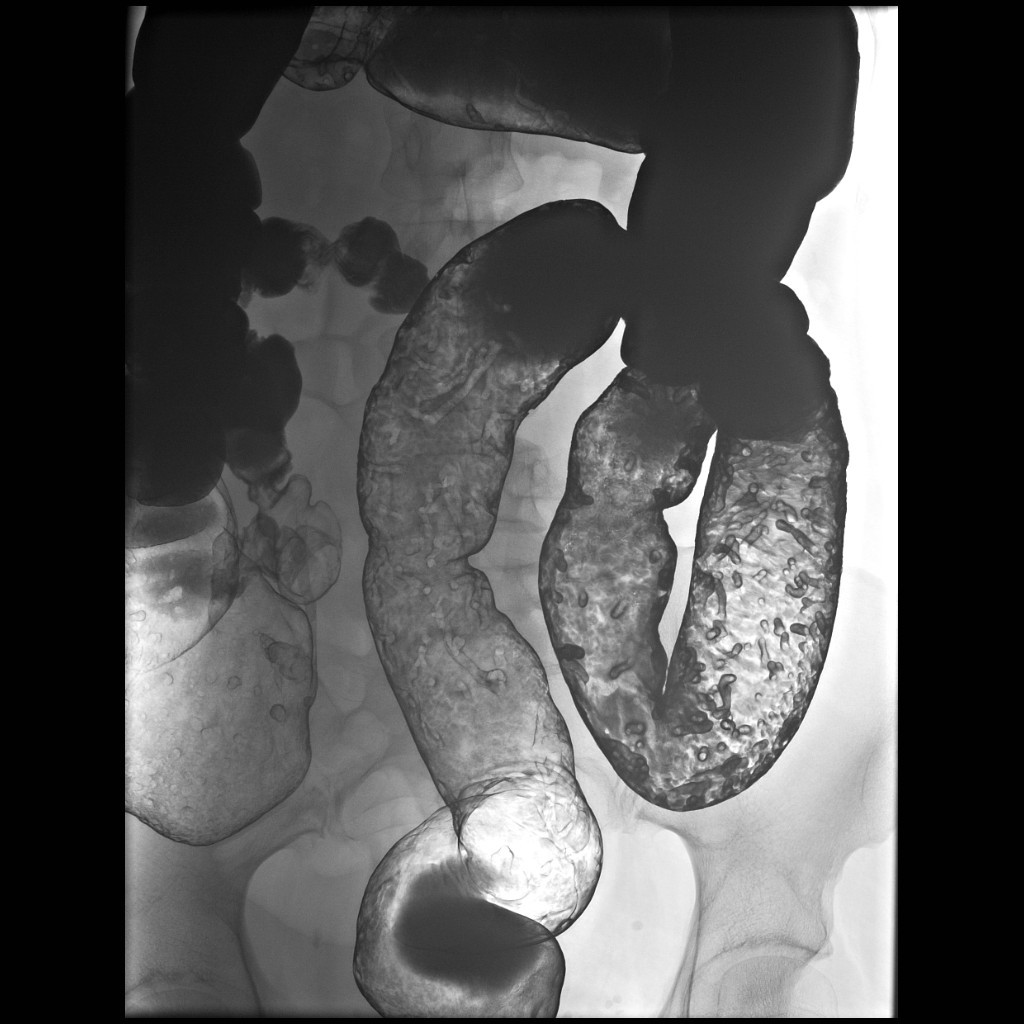

The pancreas appears bulky and shows an ill-defined isodense hypoenhancing mass measuring approximately 4.3 x 2.0 cm. There is extensive polypoidal thickening of upper gastrointestinal tract wall, involving the pylorus of stomach, duodenum, jejunum and proximal ileum. The polyps measure 5 to 30 mm and causing luminal compromise. The proximal small bowel appears distended till distal ileum and there is an ileo-ileal intussusception noted in the distal ileum. The terminal ileum and large bowel appear collapsed.

There are few enlarged non-necrotic lymph nodes noted in the mesentery, the largest lymph node measures 1.3 x 0.8 cm in size. There is a well defined oval mass measuring approximately 6.0 x 4.5 cm noted in the right adnexa. The right ovary could not be separately visualized from the mass. The mass shows post contrast enhancement and central non-enhancing necrotic region within.

Extensive polypoidal mucosal thickening predominantly affecting the upper gastrointestinal tract with pancreatic and ovarian neoplasms are likely to represent gastrointestinal polyposis syndrome most likely Peutz Jeghers Syndrome.